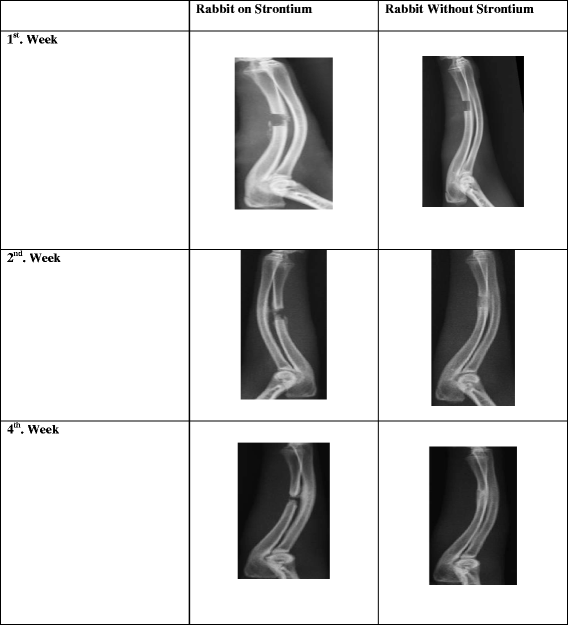

摘要:骨间隙骨折愈合是骨科手术面临的主要挑战之一。目前,这种治疗方法包括骨移植,无论是内固定还是外固定,对患者、家庭乃至社会都有重大影响。在市场上新的药物如合成骨形成剂包括特立帕肽和雷尼酸锶均用来刺激骨生长。本文从其作用机制出发,对兔桡骨骨折带骨间隙的愈合进行了研究。将十只家兔分为两组:实验组五只,对照组五只。我们在尺骨骨中创造了一个5毫米的骨间隙,同时也切除了骨膜。试验组动物接受450mg/kg雷尼酸锶每日口服给药,连续六周。每两周进行一次X射线、CT扫描和血液检查。六周后处死家兔,取桡骨和尺骨进行组织病理学检查。结果:基于X线和CT扫描结果基础上,对照组骨折愈合或骨形成速度加快。从X光检查结果来看,80%的骨折愈合。通过CT扫描,在六周研究结束时,对照组骨折的愈合率为60%。试验组没有骨折愈合。然而,组织病理学报告显示,两组均形成不同时期的愈伤组织。血清骨钙素和碱性磷酸酶在三周后基本保持不变。在六周结束时略有变化。结论:锶效应开始缓慢,虽然它可能不干扰骨细胞增殖,它可能干扰矿化和延迟骨折愈合的急性期。建议实施更大的样本量和更长的研究期,以确认我们的发现。关键词:骨折 锶 尺骨 骨钙素 碱性磷酸酶背景:延迟愈合、不愈合的治疗,畸形愈合和骨丢失对整形外科医生而言是个巨大挑战。骨折愈合障碍对患者的生活质量产生负面影响,导致医疗费用高,因为第二次手术要稳定骨折并刺激骨生长。许多情况下需要辅助措施,如骨移植,以刺激骨愈合和填补骨缺损。骨缺损修复的金标准是自体移植,但它们的使用受到供体部位的发病率和供应有限的影响。异体移植的局限性包括宿主对移植的免疫原性反应和疾病传播的可能性。为了克服这些局限性,越来越多的生物学材料正在开发有助于骨缺损的治疗。可供选择的骨替代物有自体骨或异体松质骨或皮质骨、脱钙骨基质、磷酸钙骨移植替代物或自体骨髓。除了骨移植和骨移植替代物,整形外科医生目前使用类固醇药物如特立帕肽和雷尼酸锶促进骨折愈合和骨质量的提高。一种合成代谢剂是通过增加骨量来提高骨强度,因为骨重建与骨平衡相结合。雷尼酸锶促进骨缺损的填充和提高大鼠骨愈合性能。锶核的大小与钙差不多,身体很容易吸收,将其结合到骨骼和牙釉质中。雷尼酸锶通过骨形成和骨吸收双重作用模式,提高骨微结构。这种药物被批准用于预防绝经后骨质疏松症和髋部骨折。临床前研究表明雷尼酸锶增强骨折愈合及骨整合,改进骨微结构。人类和四足动物尺骨具有相似的功能。如果尺骨折断,它通常发生在桡骨和尺骨形成关节的位置,或者尺骨与手的腕骨形成关节的地方。尺骨骨折引起剧烈疼痛,如果骨折愈合,移动受影响的关节困难甚至导致手臂畸形。骨折自然愈合的期限最长为6周左右,与对照组相比,期待雷尼酸锶治疗会触发更快的愈合。方法:使用雄性新西兰白兔,(n=5)28至32周,手术时体重范围2~2.5公斤。动物自由采食和饮水,饲养房间温度26-28°C、湿度60%。所有的外科手术都是在动物房里的操作间进行的。所有的兔子的耳朵都有一个永久的记号。手术前对动物称重。计算麻醉剂量(氯胺酮20mg/kg IM),包括镇静和肌松剂甲苯噻嗪(3mg/kg)。肌肉内注射抗生素(kombitrim 240, 1ml/ 10kg)。给兔左前腿剃毛。在整个实验过程中,所有兔子体重平均增加0.1 - 0.3公斤。手术技术:麻醉完成后,左前腿剃毛,将兔子仰卧位置于手术台上。使用碘伏消毒后,铺一次性无菌单。手术过程采用无菌技术。识别骨干尺骨骨中心,对皮肤表面标记,在计划切口处进行局部麻醉。做一个1.5厘米长的纵行切口。确定肌内隔膜,显露尺骨中轴线。分离软组织以暴露骨头,在左尺骨内侧表面的皮肤边界做长4厘米的纵行切口,在现有骨干中心标记2厘米的近端和2 cm远端。然后切开筋膜,采用钝性解剖分离尺肌,露出尺骨骨。在骨上标记了截骨的计划位置,并用一个小的不锈钢直尺测量。然后用振动锯进行截骨,小心避免损伤骨膜。在截骨过程中用生理盐水冲洗。每个尺骨都有一个5毫米的缺陷。所有家兔均接受手术,并在几天内恢复正常活动。无伤口感染。手术后一天所有动物均能自由走动。无神经系统损伤,如瘫痪、抽搐、呼吸窘迫或疼痛迹象。锶治疗:治疗组每只兔口服雷尼酸锶溶液5毫升(2克雷尼酸锶混合在10毫升蒸馏水中)连续喂养六周。宏观评价:经过尸检,去除软组织,获得桡骨和尺骨。肉眼观察骨缺损部位,并拍摄照片。X射线和CT扫描:使用X射线和CT扫描评价各组兔骨缺损愈合情况。每只兔子分别在1, 3周和6周进行扫描,以确定各组缺损愈合的进展。在全身麻醉下,将兔子准确地定位在CT扫描机右侧的位置上,左前腿抬高在样品架上。桡骨和尺骨长轴与X射线轴垂直排列。图像层厚0.6 mm,2048?×?2048像素分辨率。扫描得到的图像保存在DICOM格式中。由资深整形外科医生评估如钙化,出现愈伤组织,骨小梁的连续性。骨生长质量评价:评估初始和桥接骨痂形成。获得三维重建图像较好的观察和评价骨再生。在兔尺骨模型上,如果在骨片上观察到可见桥接的骨痂,则可以认为这种融合是成功的。桥接的骨痂需要在三个皮质上可见。我们不能做骨折愈合的临床评估,因为桡骨完整,兔子能立即负重。从射线照片上进行评估和分析各组骨生长的模式和行为。生化试验:分别在1, 3周和6周,通过耳缘静脉获取血清骨钙素、碱性磷酸酶、钙和磷酸盐。10000 x g离心10分钟。然后用相应的试剂盒分析骨钙素、ALP、钙和磷酸盐的浓度。在微孔板读数器上测量每个参数的光密度。组织病理学:尸检后,取桡骨和尺骨。标本用于进行组织病理切片。样品存放在10%的中性福尔马林溶液浸泡四天,然后用10%甲酸脱钙五天。样品用石蜡包埋,纵向切片,HE染色。切片在光学显微镜下进行放大检查。组织病理学切片由一位病理学家检查。每个标本骨折愈合的进展是定量的,基于板层骨,编织骨、软骨、纤维组织、软骨内成骨和膜内骨化的相对百分比。用X射线和CT扫描收集骨生长数据。结果:在研究结束时对锶治疗兔桡骨尺骨进行射线检查。在六周的研究结束时,没有样本显示放射性愈合。在桡骨和尺骨,而不是在骨折间隙,观察到过度的愈伤组织形成。上述研究结果表明,锶治疗不能明显改善兔尺骨骨折愈合。用Cheung法对试验组和对照组进行X线骨愈合和骨不愈合检查。尺骨骨折愈合与锶无相关性。而对照组的愈合率更高。术后1周内对所有的家兔进行检查,并进行CT扫描。没有观察到任何骨痂形成的证据,清楚地看到了0.5厘米的间隙。大约三周时,可见最小的骨痂形成。从截骨边缘开始形成愈伤组织。在尺骨和桡骨间出现更多的愈伤组织但不是在骨间隙。在六周时,只有两个样本显示放射性愈合。实验结束时,A组(锶)和B组(无锶)的兔前肢的CT扫描见图。术后第一周内对两组进行CT扫描。没有发现任何骨痂形成的证据。术后三周,缺损中心和骨边缘周围出现片状钙化。片状钙化向骨缺损中心移动。愈伤组织在缺陷区逐渐扩大。术后四周左右,近端骨痂生长较快到达中心骨痂。然后,它慢慢生长,并在六周左右见到远端骨痂。此时,没有骨折间隙。骨的生长被用来填满整个截骨部位。在6周时,骨折愈合了。新骨的直径大小小于实际缺陷。Fisher精确检验的P值为0.52。对照组,X射线愈合率给100%,CT扫描愈合率为80%。术后1, 3周、6周分别测定血清碱性磷酸酶、血钙、血清磷、血清骨钙素等生化指标。随骨痂的老化,比较血清标志物。在1, 3周和6周血清钙和磷酸盐无变化。然而,在第六周血清ALP和骨钙素水平有显著的统计学差异。组织学检查显示板层骨、编织骨、软骨和纤维组织的分级和百分比。在不连续骨标本中,板层骨的存在可能是由桡骨造成的。然而,锶治疗组和未治疗组的愈合无显著差异。结论:兔模型雷尼酸锶治疗没有发现促进骨愈合,事实上可能会延迟骨形成,特别是在骨折愈合的早期阶段伴随骨间隙。有必要进行进一步的研究,以更大的动物模型来确定雷尼酸锶的作用。